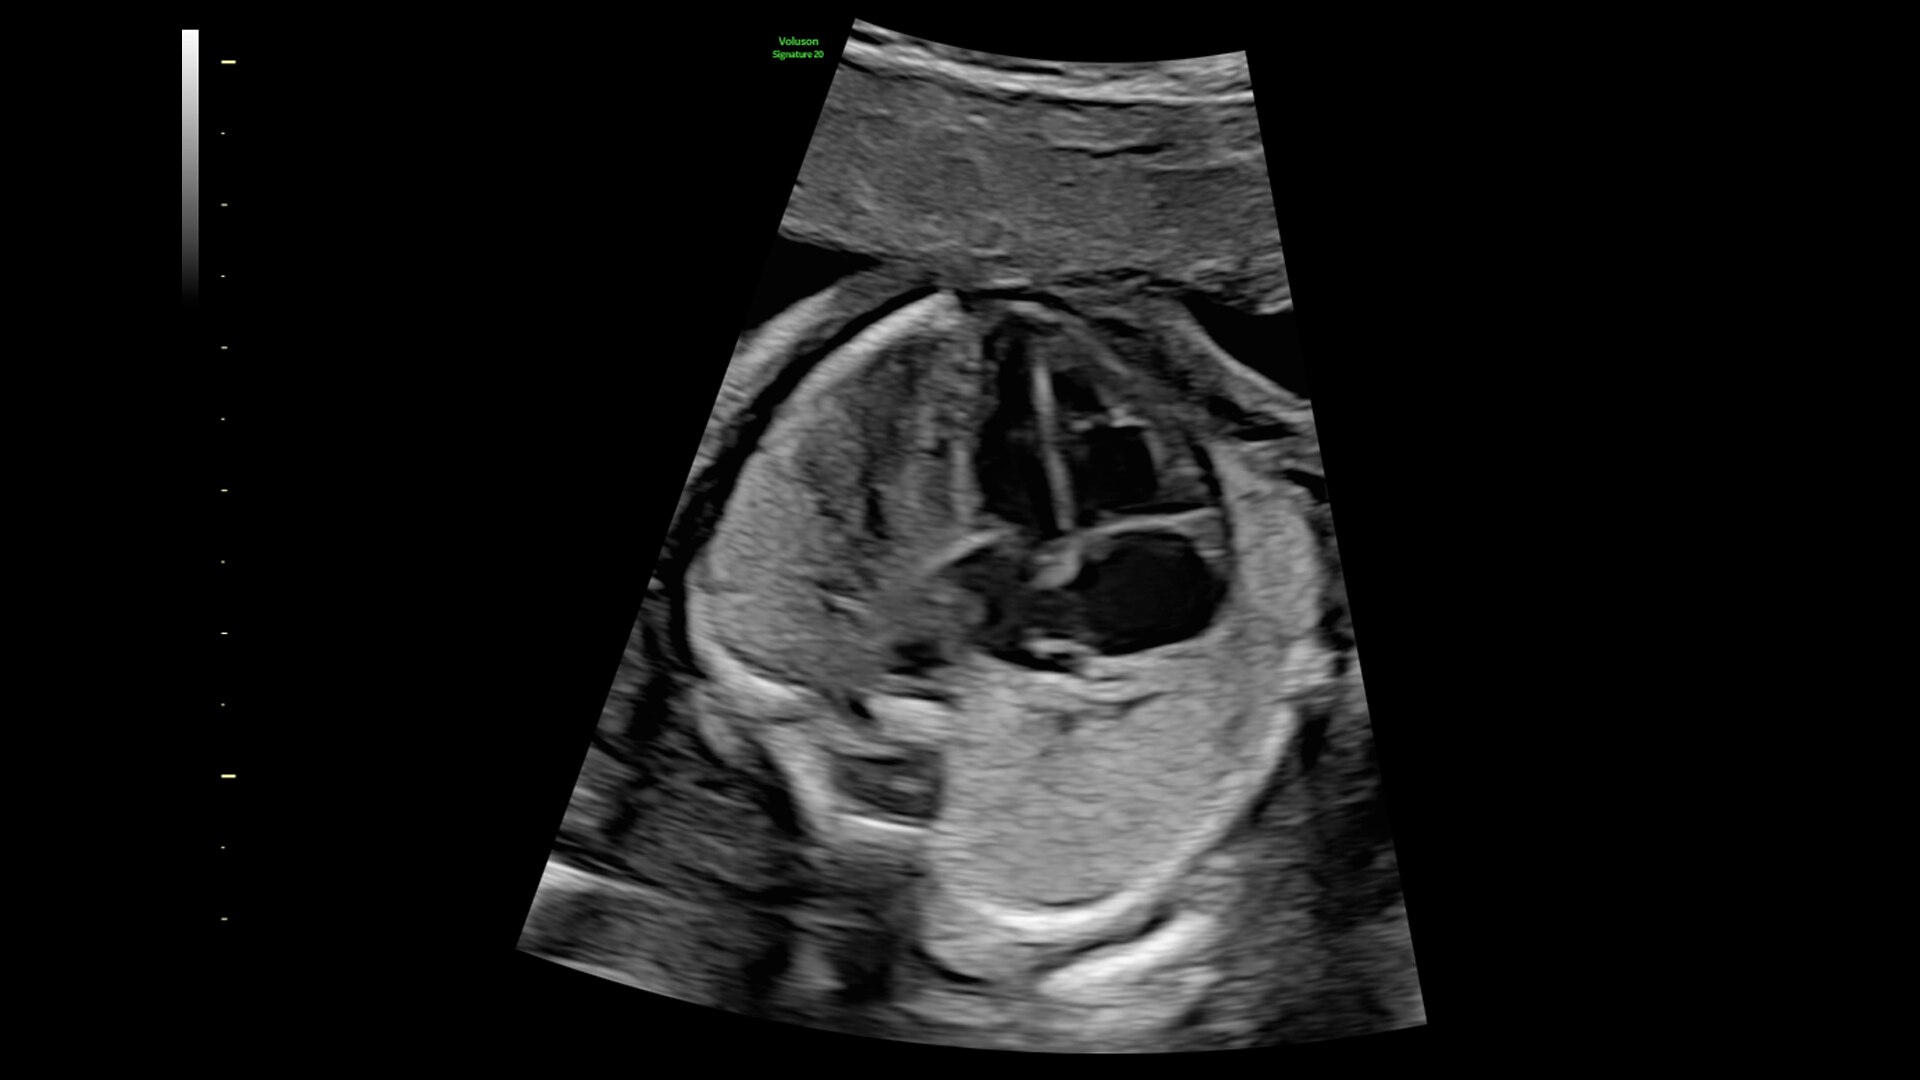

SonoLyst

SonoLyst* reduces the time to complete the standard ISUOG 2nd trimester exam requirements by 40%. And with SonoLyst live, it means no more stopping to freeze, annotate, or store.

fetalHS

Reduce time to assess fetal heart by 48% with fetalHS. fetalHS provides a step-by-step guidance that uses AI to help identify fetal situs and normal fetal heart anatomy using the 4-Chamber Heart, 3-Vessel View/3-Vessels and Trachea View, and Cardiac Axis.